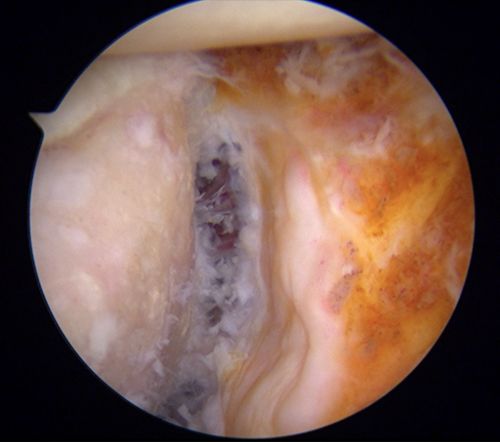

镜下完美完成骨块固定。

由于左肩脱位症状极重,患者入院当天早上再次发生脱位。CT检查发现,左肩胛盂有较大的骨缺损,缺损面积大约为15X35mm,相当于正常肩胛盂面积的30%。目前,针对此类肩胛盂(骨缺损>20%)修复,指南建议使用临近的喙突移植肩胛骨以修补骨性缺损(Lartarjet术),但不幸的是患者喙突发育不良,小于骨缺损体积,Lartarjet术没有条件实施。王靖果断决定利用髂骨来修复肩胛盂。该手术在关节镜下实施难度极大,是省内首次报道,同时也为肩关节脱位合并巨大肩胛盂缺损患者提供了肩关节镜微创治疗的新方法。术后复查CT可见左肩胛盂前方有一块移植髂骨块挡住了肱骨头脱位的轨迹。